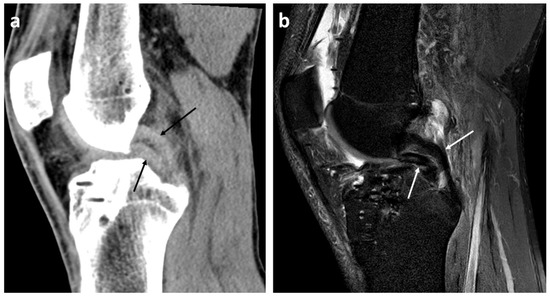

- Presence or absence (yes/no) of mentioned radiological signs of dislocated bucket handle meniscal tears (double delta sign, disproportional posterior horn sign, double PCL sign)